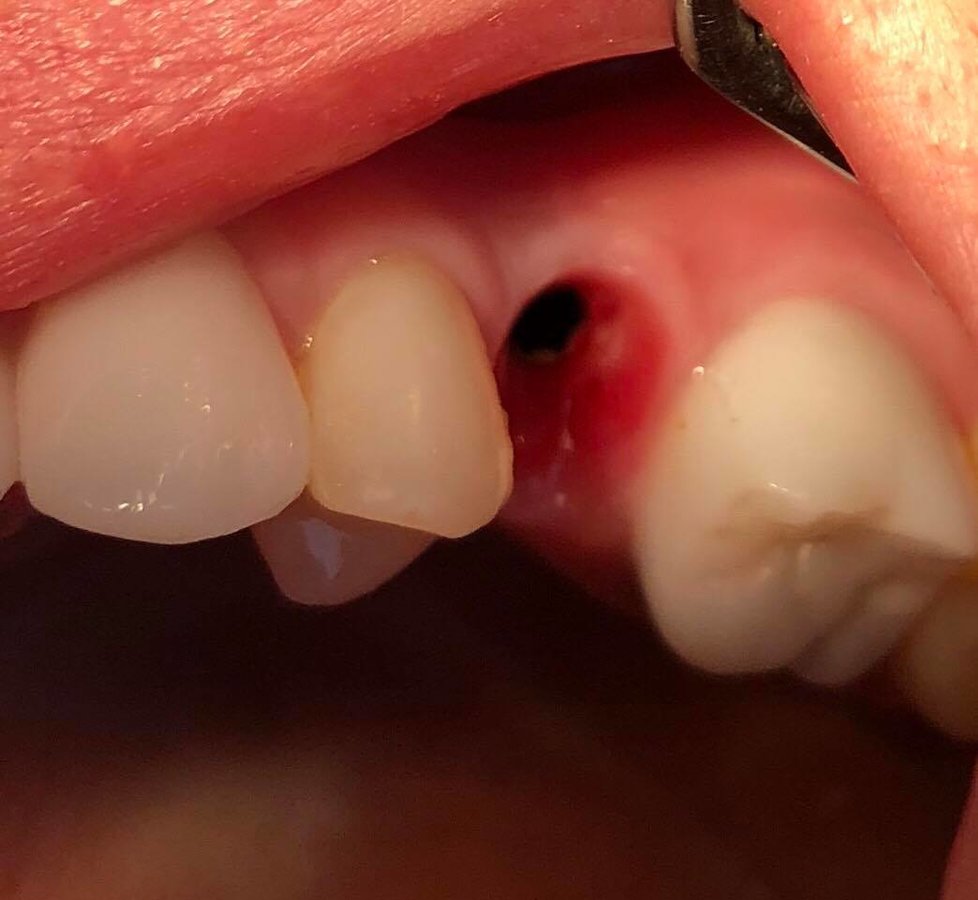

Dental Implants $445

Extractions $45